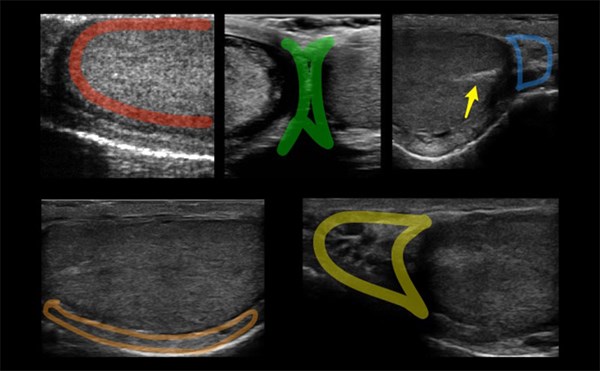

Needle Orientation: In-Plane vs Out-of-Plane Approach

Figure 1. Needle Orientations

2 needle orientations for ultrasound guided procedures, the in-plane and out-of-plane approach